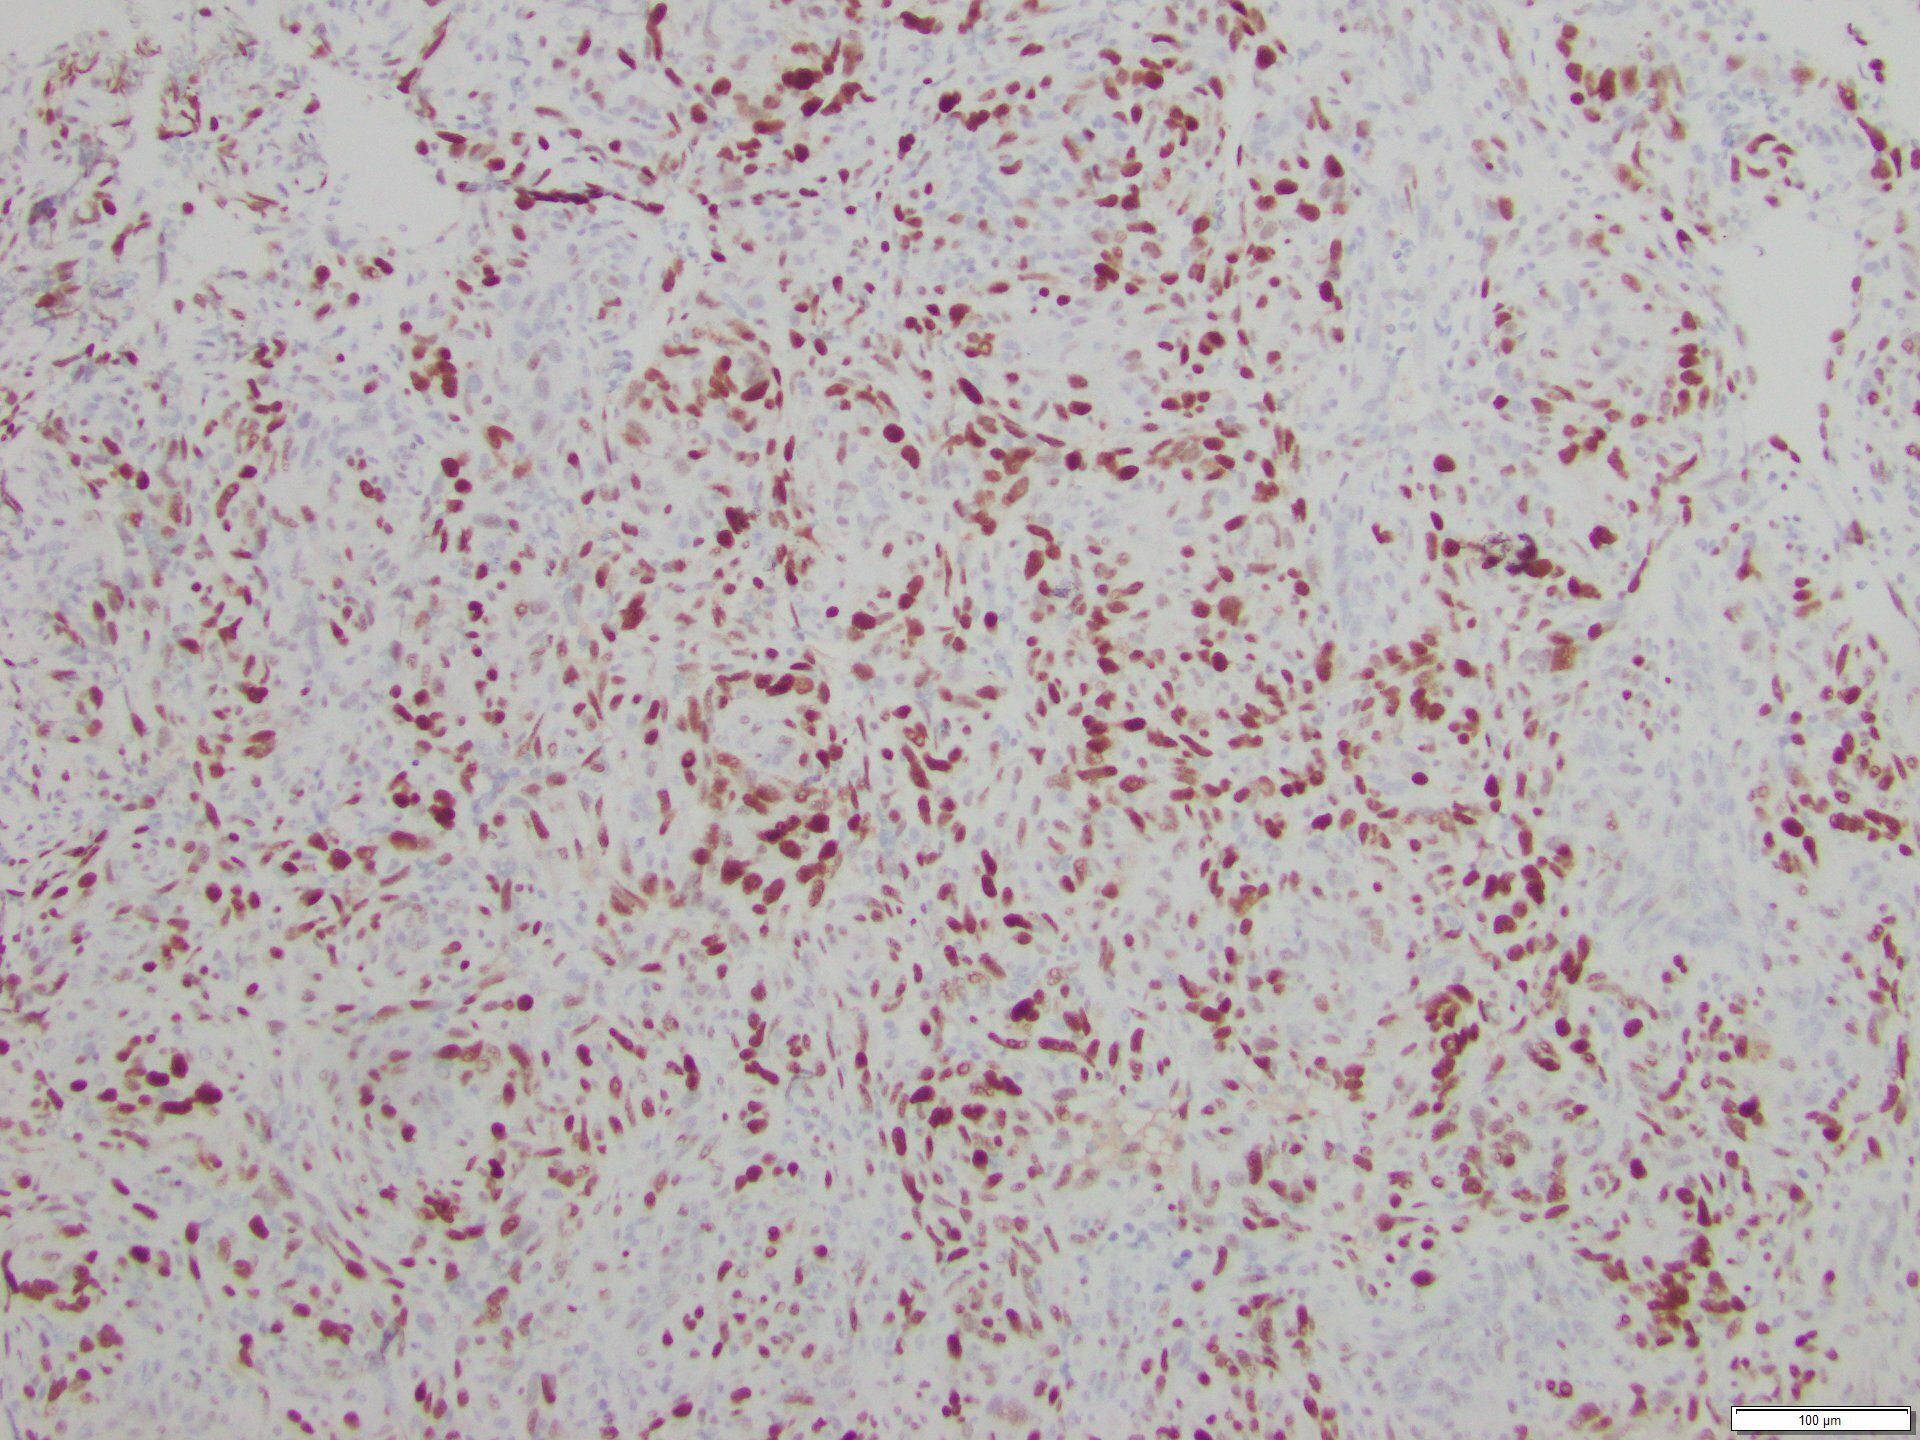

The skin lesion was completely excised and sent to pathology for diagnosis (Figures 1-3). The lesion is hypercellular with an infiltrative, predominantly solid, growth pattern in the dermis and subcutaneous tissue. It is highly vascular and has complex anastomosing and poorly formed vascular channels. The tumor cells are large, pleomorphic, have vesicular chromatin, and prominent nucleoli. There are frequent mitoses and extravasated red blood cells throughout. Immunohistochemistry shows the tumor cells are diffusely positive for ERG (Figure 4) and c-MYC (Figure 5) while negative for pan-cytokeratin (Figure 6) and GATA3. Subsequently, the patient underwent a left total mastectomy.